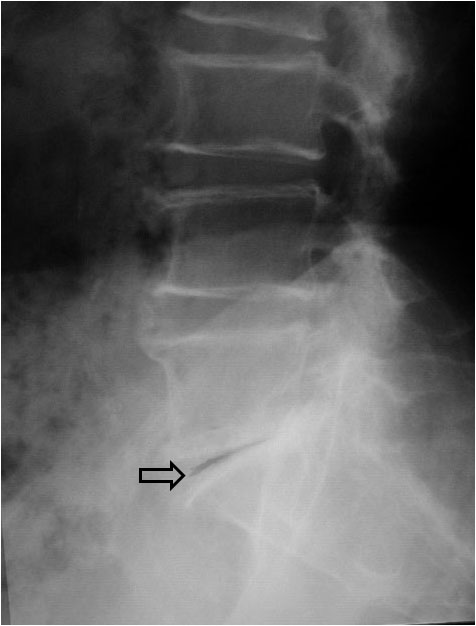

SIGNO DEL SURCO FEMORAL LATERAL

Signo indirecto de rotura del ligamento cruzado anterior (LCA) en la radiografía simple. Se trata de una depresión anormalmente profunda del surco cóndilo-patelar lateral o surco femoral lateral (flecha). Este surco es una pequeña depresión normal en la superficie articular del cóndilo, entre la curvatura que articula con la rótula y la que gira sobre la tibia. El surco anormalmente profundo se produce en la fractura osteocondral impactada, que acontece al tiempo que la rotura del LCA, ya que el mecanismo de ambas lesiones es el mismo: rotación de la articulación y valgo forzado, en el que chocan el platillo tibial contra el cóndilo femoral.